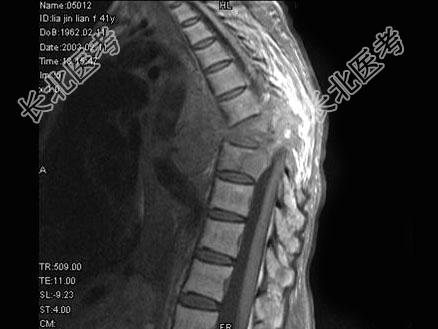

- 单项选择题女,41岁, 胸背部疼痛,肢体活动感觉障碍2年余, MRI检查见T

、T

椎体及附件骨质破坏,并向周围形成巨大肿块影, 呈T1低信号为主,T2加权有多个大小不一圆形混杂高信号, 边界清楚,最可能的诊断是 ( )